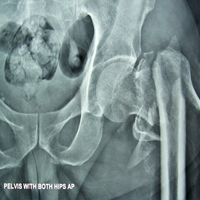

Case:8 Polytrauma

Patient having closed segmented fracture midshaft & lower 1/3 Tibia with closed fracture superior & inferior pubic rami right side with pelvis fracture following vehicular accident wastreated with intramedullary nail for fracture tibia and external fixator for fracture pelvis.

Pre-Op

Immdiate Post-op

Ex fix with frame